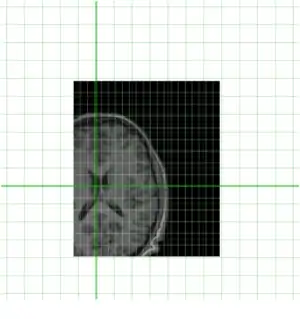

To get an idea of how they currently overlay I have put them together below

Clearly they are not aligned or "registered" to each other so we have to use a tool such as minctracc or mritoself in order to align them as such: